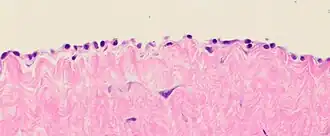

![Cytology of the normal mesothelial cells that line the peritoneum, with typical features.[9] Wright's stain](./_assets_/Cytology_of_normal_mesothelium.jpg) Cytology of the normal mesothelial cells that line the peritoneum, with typical features.[9] Wright's stain

Cytology of the normal mesothelial cells that line the peritoneum, with typical features.[9] Wright's stain -